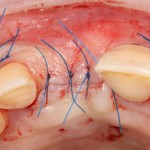

В этом случае остеопластика делается отдельной процедурой. Ее принципы точно те же, но уже без импланта. Например:

Имплантировать в таких условиях — заведомо обрекать себя на хреновый, с точки зрения эстетики и функциональности, результат. Поэтому первым этапом проводим остеопластику. Объем небольшой, использовать в таких объемах костный блок не очень рационально. Воспользуемся аутокостной стружкой и мембраной.

Сначала фиксируется BioGide. Это легко:

Затем укладывается и конфигурируется аутокостная стружка:

Если после этого BioGide намочить физраствором, им легко укрыть получившийся объем:

Для надежности можно зафиксировать пинами:

Ну и, швы: